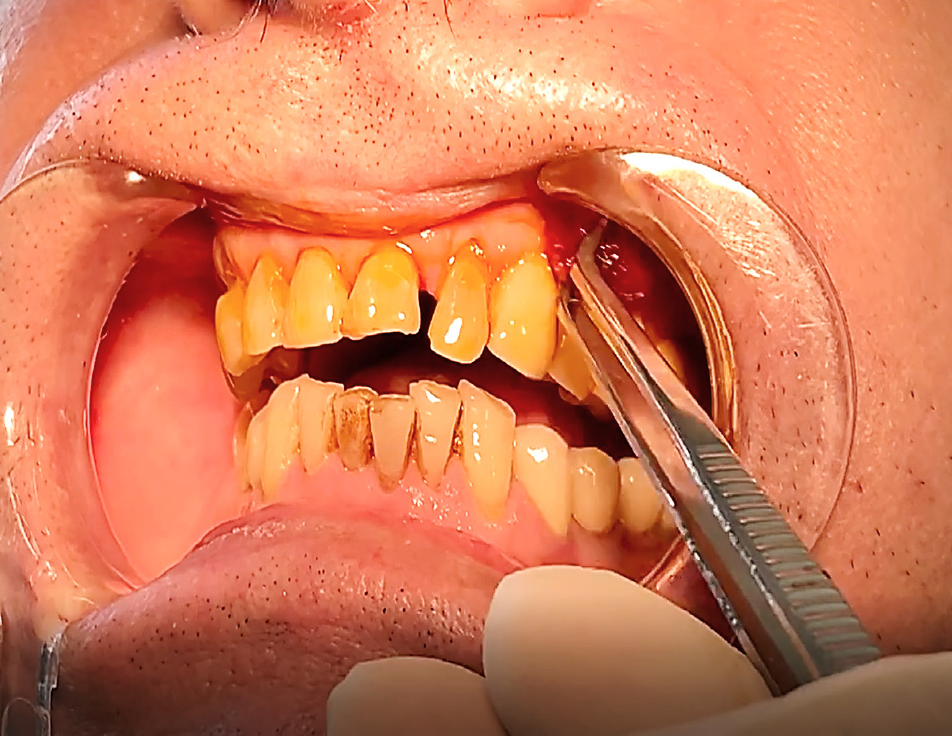

Клинический успех лечения оценивали путем соотношения шансов, который выражается соотношением повышенного риска и нормальной восприимчивости. Для определения факторов риска, так называемых факторов-предикторов, которые могут спровоцировать развитие воспаление зубодесневого комплекса, применяли следующие индексы – приблизительный индекс зубного налета – API, индекс сосочковой кровоточивости (PBI), пародонтальный индекс нуждаемости в лечении (CPITN), индекс рецессии десны по Miller. Алгоритм диагностики и ведения пациентов заключался в следующем. Проводилось комплексное поэтапное обследование. На первом этапе собран анамнез жизни и заболеваний пациента с выявлением существующих рисков (приобретенный или генетический уровень). На втором этапе произведен сбор клинических данных до начала проведения подготовки к ортопедическому лечению: оценка пародонтального статуса, уровня рецессии десны, вовлечение фуркации, активность карманов, подвижность зубов, оценка воспаления десны с проведением гигиенических индексов (рис. 2).

На первостепенном уровне проведена запись клинических данных («золотой стандарт»). Затем выполнена визуальная диагностика с помощью стоматологического зеркала, особо внимание уделяли скоплению зубного налета, выявление рецессии десны (рис. 3). Клинический осмотр на каждом этапе включал измерение глубины зондирования кармана и потери прикрепления (рис. 4). Сила зондирования составляла 0,20 Н, что соответствует 25 г.

До начала проведения подготовки зубодесневого комплекса у пациентов с низкой коронкой опорных зубов была определена гигиена полости рта, на основании показателей которых выполнена профессиональная чистка зубов. Так, API составил 69 %, индекс сосочковой кровоточивости PBI – 28 %, CPITN – (2,1 ± 0,3) балла. При зондировании зубодесневой борозды глубина погружения определена в (2,7 ± 0,2) мм. Далее пациентам согласно рандомизации выполнена одна из методик подготовки зубодесневого комплекса к ортопедическому лечению – гингивэктомия, гингиворетракция и гингивопластика (рис. 5). Спустя 14 дней при оценке клинических показателей были получены следующие значения (табл. 1).